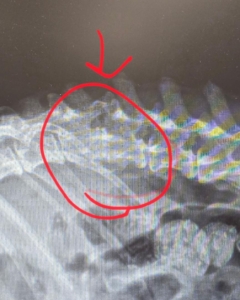

Update on Our little miracle Chihuahua. He looks like he has some fused vertebrae, whether previous trauma or disk problem. He’s very malnourished so he will be on special food. His remaining teeth will need a dental. He is getting medication for pain management.